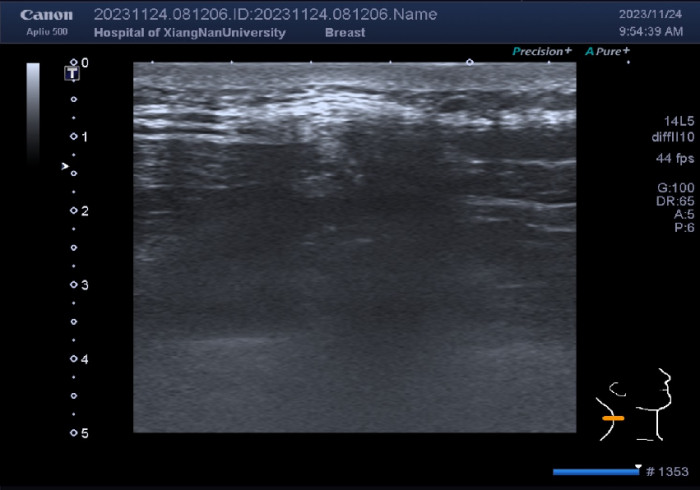

本网讯(通讯员 胡楠)近日,49岁的黎女士突然发现自己的颈后部长了一个椭圆形的包块,仰头时比较明显,低下头时包块就消失了,遂来到我院就诊。超声检查发现黎女士颈后部软组织层内有一个低回声团块向外凸起,诊断为项韧带松弛。这是什么原因呢?原来竟是长时间低头的祸。